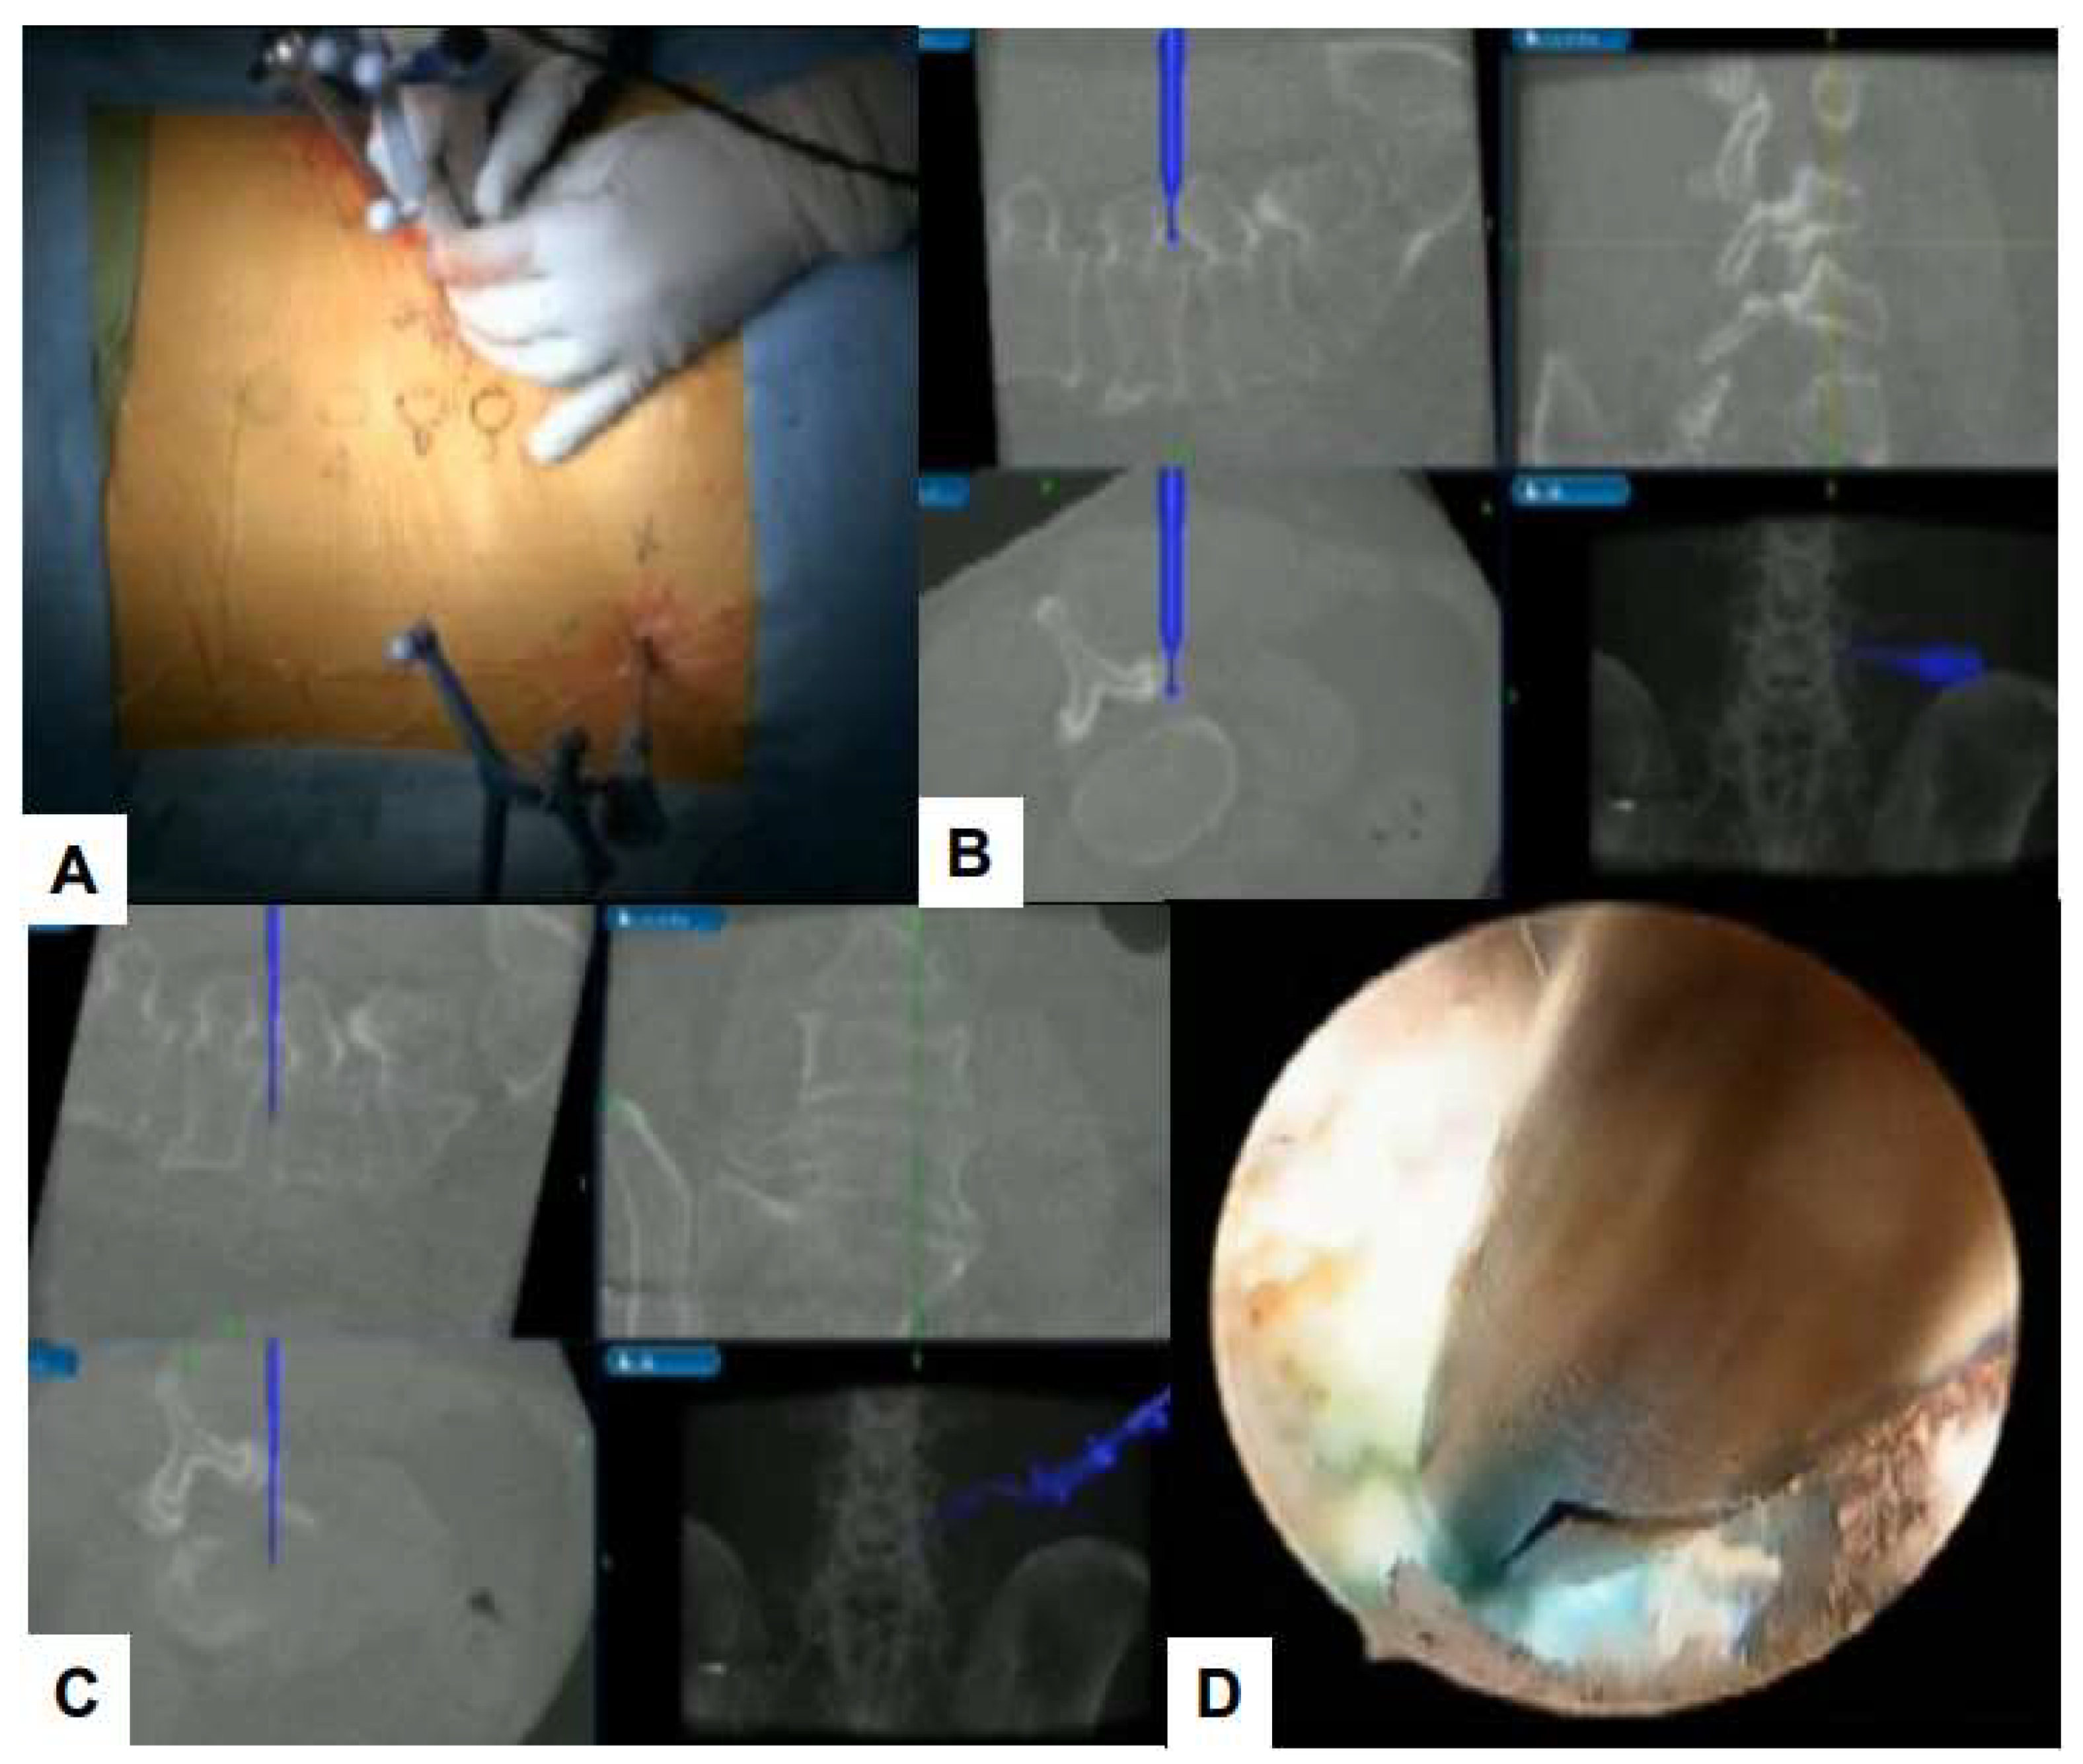

6. Latest Advances

6.1. Navigation

6.2. Ultraresolution and Three Dimensional Endoscopes

6.3. Robot-Assisted Endoscopic Surgery